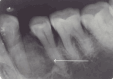

Benign osseous tumors of mesodermal origin that are included within the group of fibro-osseous lesions include cemento-ossifying fibromas (COFs). The fibrocellular component of these diseases originates from the periodontal ligament, which deposits bone and cementum encased in fibrous tissue. It typically appears in the mandible and presents as a solitary, nonaggressive, slowly developing, asymptomatic, expansile lesion, rarely occurring in the maxilla. The only intervention that proved to be successful in producing excellent outcomes and that may be regarded as a final therapeutic option is the complete surgical removal of COFs. Presenting herein is a case report describing a painless and expansile mass in the left mandibular region, histopathologically diagnosed as COF.